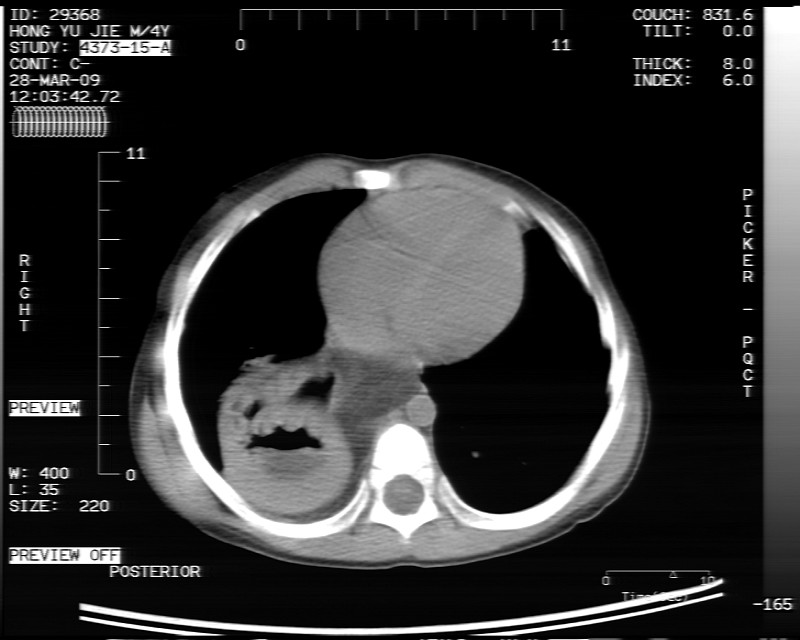

标题: PED1814:胸片体检发现右下肺病变。

男性,3岁,斜疝术前常规检查胸片体检发现右下肺病变。咳嗽,无发烧。

内有气体,液平面,考虑食管裂孔疝可能性大。建议食道钡透。

有液气平面,前部肺纹理聚集(受压改变),周围肺野及相邻胸膜清晰,支持膈疝,可吞服造影剂看一下。

考虑膈疝(右侧胸腹膜裂孔疝?)。